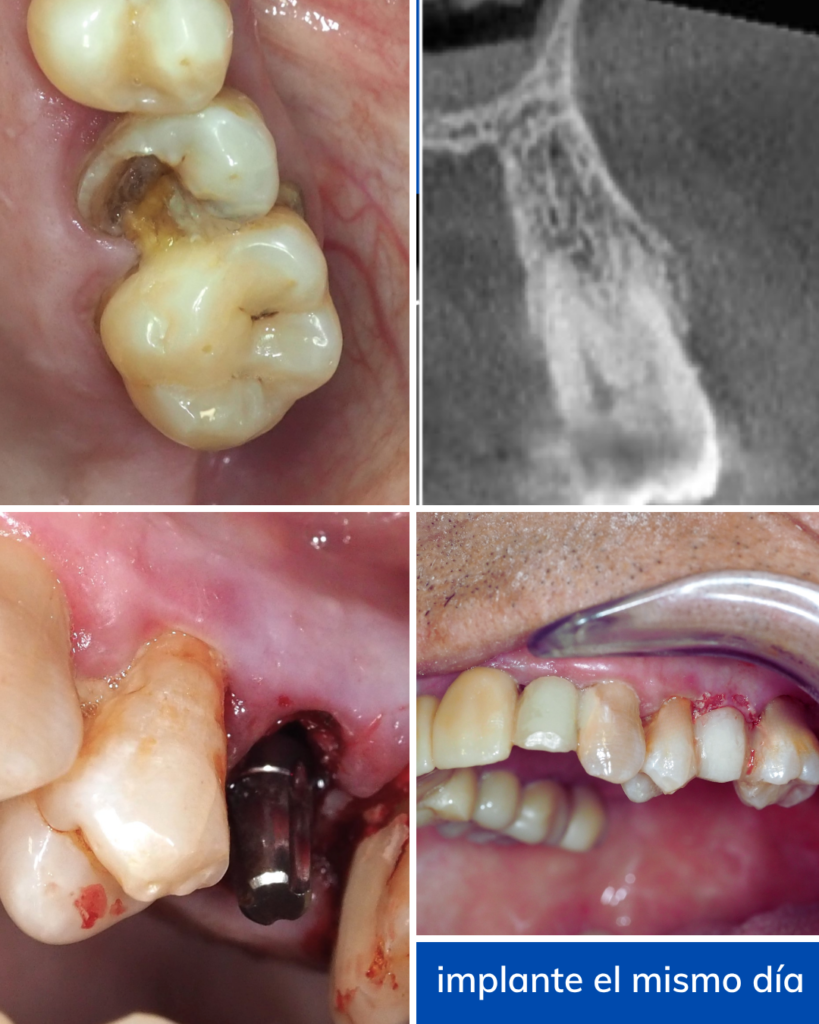

Un caso real: sonrisa recuperada en horas

Un paciente llegó a nuestra clínica con una pieza dañada. Necesitaba una solución rápida, efectiva y sin largas esperas. Su principal preocupación era volver a sonreír y comer con normalidad sin un proceso largo.

- Extracción y Colocación exprés: En una sola visita, se realizo la extracción e insertamos el implante monofásico en el hueso maxilar.

- Prótesis inmediata: Ajustamos una corona provisional justo después de la cirugía.

- Resultado: El paciente salió de la consulta con un diente funcional y estético.